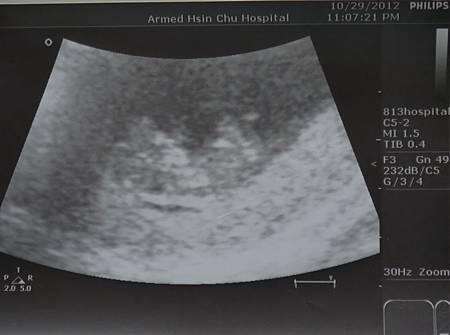

【10W】小ET形成

孕期邁入了第十週

照慣例的躺上小床會吾兒

小籠包量量身高

只有3.19公分

好小喔

雖然現在手和腳都還小小的

可是這看起來好像在翹腳喔

不過這主要是醫生要看頸部透明帶啦